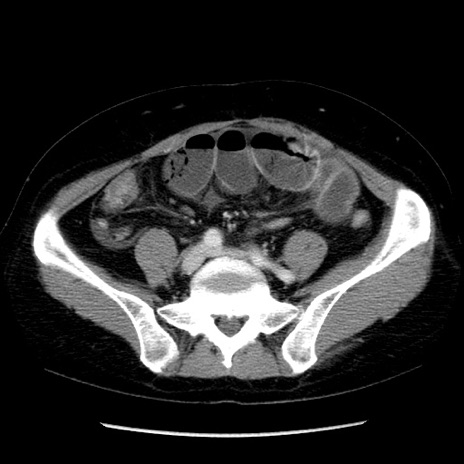

症例6(横断像)

【症例】50歳代女性

【主訴】下腹部痛

【現病歴】本日朝より下痢2回あり。 昼食を食べた後、嘔吐3回、下腹部痛認め、症状軽快せず、当院救急搬送。

最終食事:本日昼(生ものなし)。 昨日の夜、刺身を食ぺたとのこと。周囲に同様の症状の者なし。普段、排便は毎日あるとのこと。

【既往歴】卵巣癌術後(8年前に当院で卵巣摘出)

【身体所見】 意識清明、腹部:平坦、腸蠕動音→、やや硬、下腹部自発痛・圧痛あり、反跳痛あり、筋性防御なし。

【データ】WBC 16000、CRP 0.01